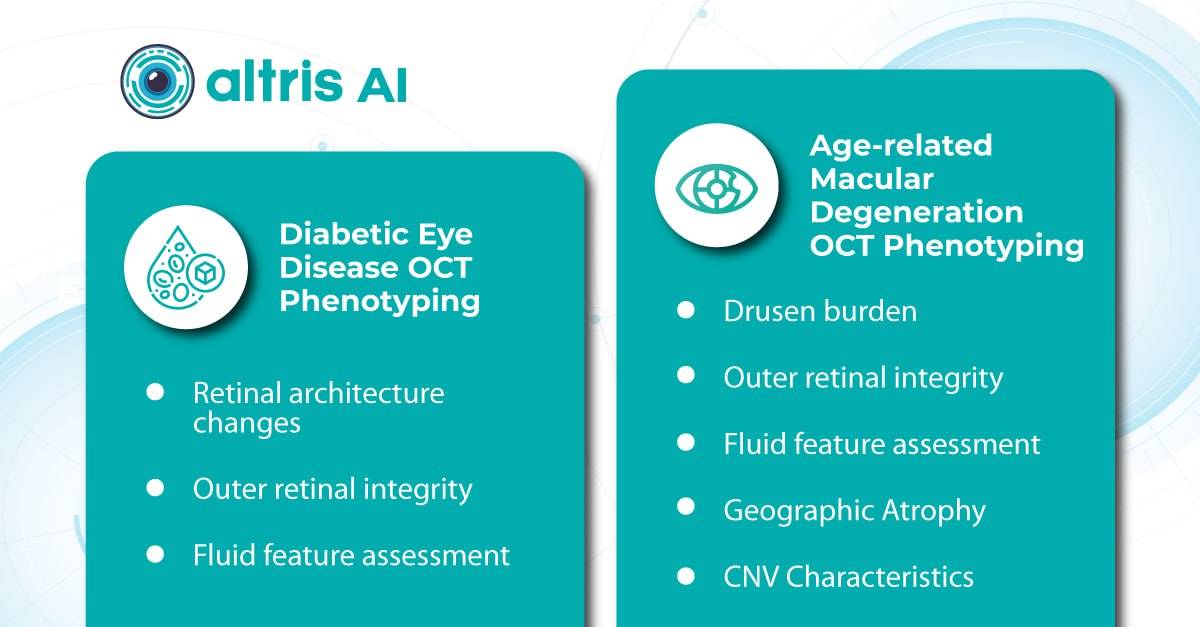

In this article, we will explore how AI for ophthalmic drug development transforms the landscape by accelerating the identification of biomarkers for conditions like diabetic retinopathy and age-related macular degeneration, ensuring the right patients are enrolled in trials, and providing quantitative metrics for evaluating treatment efficacy.

In ophthalmology, AI-powered analysis of OCT scans can provide precise, quantitative measurements of retinal thickness, fluid volume, and other biomarkers relevant to diseases like diabetic retinopathy and age-related macular degeneration. These measurements can aid in diagnosis, disease staging, treatment monitoring, and prediction of treatment response.

Systems like Altris for pathology detection and segmentation enabled automated disease characterization and longitudinal monitoring of therapeutic response in AMD. Multiple studies have demonstrated the value of volumetric fluid characterization, compartment-specific OCT feature evaluation, and subretinal fibrosis and hyperreflective material quantification.

A study has shown the potential of AI to predict conversion from early or intermediate non-neovascular AMD to the neovascular form, using quantitative imaging features like drusen shape and volume.

The extraction of quantitative fluid features and assessment of retinal multi-layer segmentation from OCT scans have offered valuable insights into disease prognosis and longitudinal dynamics of Diabetic Retinopathy.

A recent study demonstrated that quantitative improvement in ellipsoid zone integrity following anti-VEGF therapy for DME significantly correlated with visual function recovery. Furthermore, novel imaging biomarkers, such as the retinal fluid index (RFI), are emerging as tools for precisely monitoring treatment response. Studies have shown that early RFI volatility can predict long-term instability in visual outcomes after treatment.

Building on these advancements, researchers are now exploring the relationship between imaging biomarkers and underlying disease pathways. A recent study linked levels of various cytokines, including VEGF, MCP-1, and IL-6, with specific OCT-derived biomarkers like fluid parameters and outer retinal integrity.

This transition to quantitative analysis is particularly evident in the study of AMD. For instance, non-neovascular (dry) AMD has been extensively evaluated using various imaging biomarkers, such as intraretinal hyper-reflective foci, complex drusenoid lesions, subretinal drusenoid deposits, and drusen burden.

While SD-OCT has traditionally described these features qualitatively, recent studies have demonstrated the predictive power of quantitative measures like ellipsoid zone integrity, sub-RPE compartment thickness, and automated drusen volume quantification.

These quantitative biomarkers have shown stronger associations with disease progression than qualitative features, particularly in predicting the development of geographic atrophy.

This predictive power of AI extends to diabetic retinopathy as well. In DR, quantitative measures like central subfield retinal thickness and retinal nerve fiber layer thickness have been linked to disease severity. Disruption of retinal inner layers has been associated with worse visual acuity, and its presence is highly specific for macular nonperfusion. Both DRIL and outer retinal disruption are linked to visual acuity in DR and diabetic macular edema.

Furthermore, morphological signs like hyperreflective foci, representing lipid extravasation and inflammatory cell aggregates, have emerged as potential biomarkers for monitoring inflammatory activity in diabetic eye disease. AI-powered segmentation and quantification of HRF can track changes in response to anti-VEGF and steroid injections.